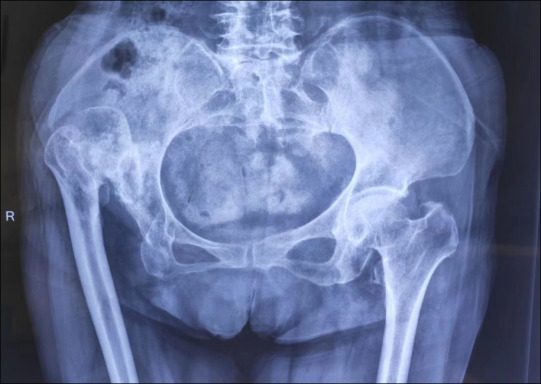

吴战坡 骨科执行主任,主任医师,骨科博士,副教授,硕士研究生导师。 江苏省中西医结合骨伤委员会委员,南京市医学会骨科分会委员,中华医学会河北省分会足踝外科专业学组委员,河北省老年医学会骨与关节损伤专业委员会常委。河北省中西医结合学会骨伤科委员会委员。南京市中医药学会外治委员会副主任委员。发表SCI论文6篇,中华医学会论文5篇,中文核心20余篇。参与编写专著3部,任编委。获国家发明专利一项。参与省市级多项科研课题,2017年获省级科技进步二等奖一项。 擅长诊断处理骨科各部位创伤及保肢治疗,骨盆骨折及四肢关节内骨折、髋、膝关节置换及翻修手术,膝髋关节病的阶梯化治疗及关节镜手术、脊柱骨折及颈腰椎间盘突出症手术治疗、各种儿童骨折及矫形手术等。指导下级医师及研究生的临床及科研工作。 高级专家门诊时间:每周三。 在南京市溧水区人民医院骨科,一线医护工作中,每天都发生着许许多多的动人故事:一次成功的抢救,一次艰苦的手术,乃至一句叮咛,一个微笑,落在患者眼里,都能化作无限的感动。溧医骨科人始终肩负着“病人至上、服务第一”的使命,以医者仁心谱写一曲曲生命赞歌。 一路风尘一路歌,兢兢业业践初心。翻开骨科执行主任吴战坡的履历,一位医者刻苦学习、积极钻研业务的生动形象呼之欲出:吴战坡主任通过不断刻苦学习与进步,在全军最高学府解放军医学院(301医院)获骨科硕士学位,后师从中国工程院院士张英泽教授,获得骨科博士学位。主任医师,副教授,硕士生导师。2018年通过人才引进来到南京市溧水区人民医院。擅长处理骨科各部位创伤及保肢治疗,骨盆骨折及四肢关节内骨折、髋、膝关节置换及翻修手术,膝髋关节病的阶梯化治疗及关节镜手术、脊柱骨折及颈腰椎间盘突出症手术治疗、各种儿童骨折及矫形手术等。工作之余,他勤奋好学,精益求精,通过微信课堂、手术视频、英文杂志等各种途径了解最新的医学动态,每年均多次参加省内外各种学术会议,聆听著名专家学者的学术讲座,开阔视野,扩大知识面,与时俱进。目前担任的学术任职有:江苏省中西医结合骨伤委员会委员;南京市医学会骨科分会委员,中华医学会河北省分会足踝外科专业学组委员;河北省老年医学会骨与关节损伤专业委员会常委;河北省中西医结合学会骨伤科委员会委员;南京市中医药学会外治委员会副主任委员。吴战坡主任不但医术高超,在学术方面也是硕果累累,已发表SCI论文6篇;中华医学会论文5篇;中文核心20余篇;参与编写医学专业著作3部;获国家发明专利一项;参与省市级多项科研课题,2017年获省级科技进步二等奖一项。 案例一 2021年,女性患者刘某,68岁,因先天性髋关节脱位,肢体短缩,严重影响生活质量,辗转多地治疗后无效,多方打听得知溧水区人民医院骨科吴战坡主任是关节疾病的诊疗专家,遂慕名而来。吴战坡主任格外重视,对其进行了仔细专科查体及影像学评估,诊断为右侧先天性髋关节脱位,关节强直,此类手术难度大,风险高,以往此类患者须请上级医院专家会诊或者转院上级医院治疗。吴战坡主任经过详细的术前讨论及准备后,成功开展了溧水区内首例高脱位髋关节置换手术,此例手术的成功开展,填补了我院骨科技术在该领域的空白,标志着我院关节骨科在关节疾病治疗上的又一进步,在溧水区打响了自家门口就有关节专家的招牌。 近几年,关节外科在吴战坡主任及其团队的不断努力下,成功开展了数十例复杂的人工全髋关节置换手术,这其中包括强直髋关节和髋关节翻修等等。在过去,这类患者往往需要乘坐数小时的车程去南京上级医院就诊,而现在,名医在溧水,让老百姓花更少的时间,在家门口就能享受到专家看病。这类复杂手术的成功开展,标志着我院关节骨科的又上一台阶。 案例二 患者邰某,男性,65岁,数年前因外伤致左胫骨平台骨折,未经正规治疗,遗留膝关节外翻位畸形,后畸形逐渐加重,疼痛明显,无法行走,经人介绍来吴战坡主任门诊就医,膝关节外翻治疗难度较内翻膝困难,而严重外翻膝的治疗更加复杂,严重外翻膝由于后侧、外侧组织挛缩严重,内侧入路不易松解,且外侧结构多,稳定性远低于内侧,关节外科医生很少选择此入路,操作不当会造成术中操作困难,增加创伤,影响术后功能。患者邰某膝关节外翻是由于骨折后畸形愈合所致,周围结构失去正常解剖关系,大量骨痂形成,后外侧软组织挛缩严重,内侧松弛,髌骨脱位,如何有效治疗是骨科关节外科医生面临的一项挑战。吴战坡主任不畏困难,带领团队术前进行详细的讨论和准备,顺利完成了膝关节的置换手术。术后患者恢复状况良好,对治疗效果非常满意。 医生常常需要了解许多领域的知识,我们常常说医学的对象是人,人不仅是自然个体而且是社会成员,除了医学知识和技术,医生还需要了解社会科学知识,从社会的背景下为患者考量治疗的方案和目标,才能真正将医生治疗的目的与患者治疗的期望结合起来。溧水区人民医院骨科作为南京市重点专科,吴战坡教授带领团队在关节置换和骨盆疾病的治疗的主攻方向上积极开展新技术、新项目,开展的髋、膝关节置换治疗水平处于本地区领先地位,优质的医疗技术服务辐射溧水周边高淳、江宁地区,甚至造福了许多省外病人。 在专业的领域做到极致,探索疾病致病机理最艰深神秘的领域,让更多患者接受更高质量的治疗,是吴战坡作为医生的执着和坚守。医者仁心,对于希望患者不再为疾病所苦的强烈期望和精益求精的职业精神,引领着无数医生不断深化对于疾病的研究和认识,在医学的领域勇攀高峰,吴战坡正是这一信念的坚定践行者。 以爱为医 奔赴山海